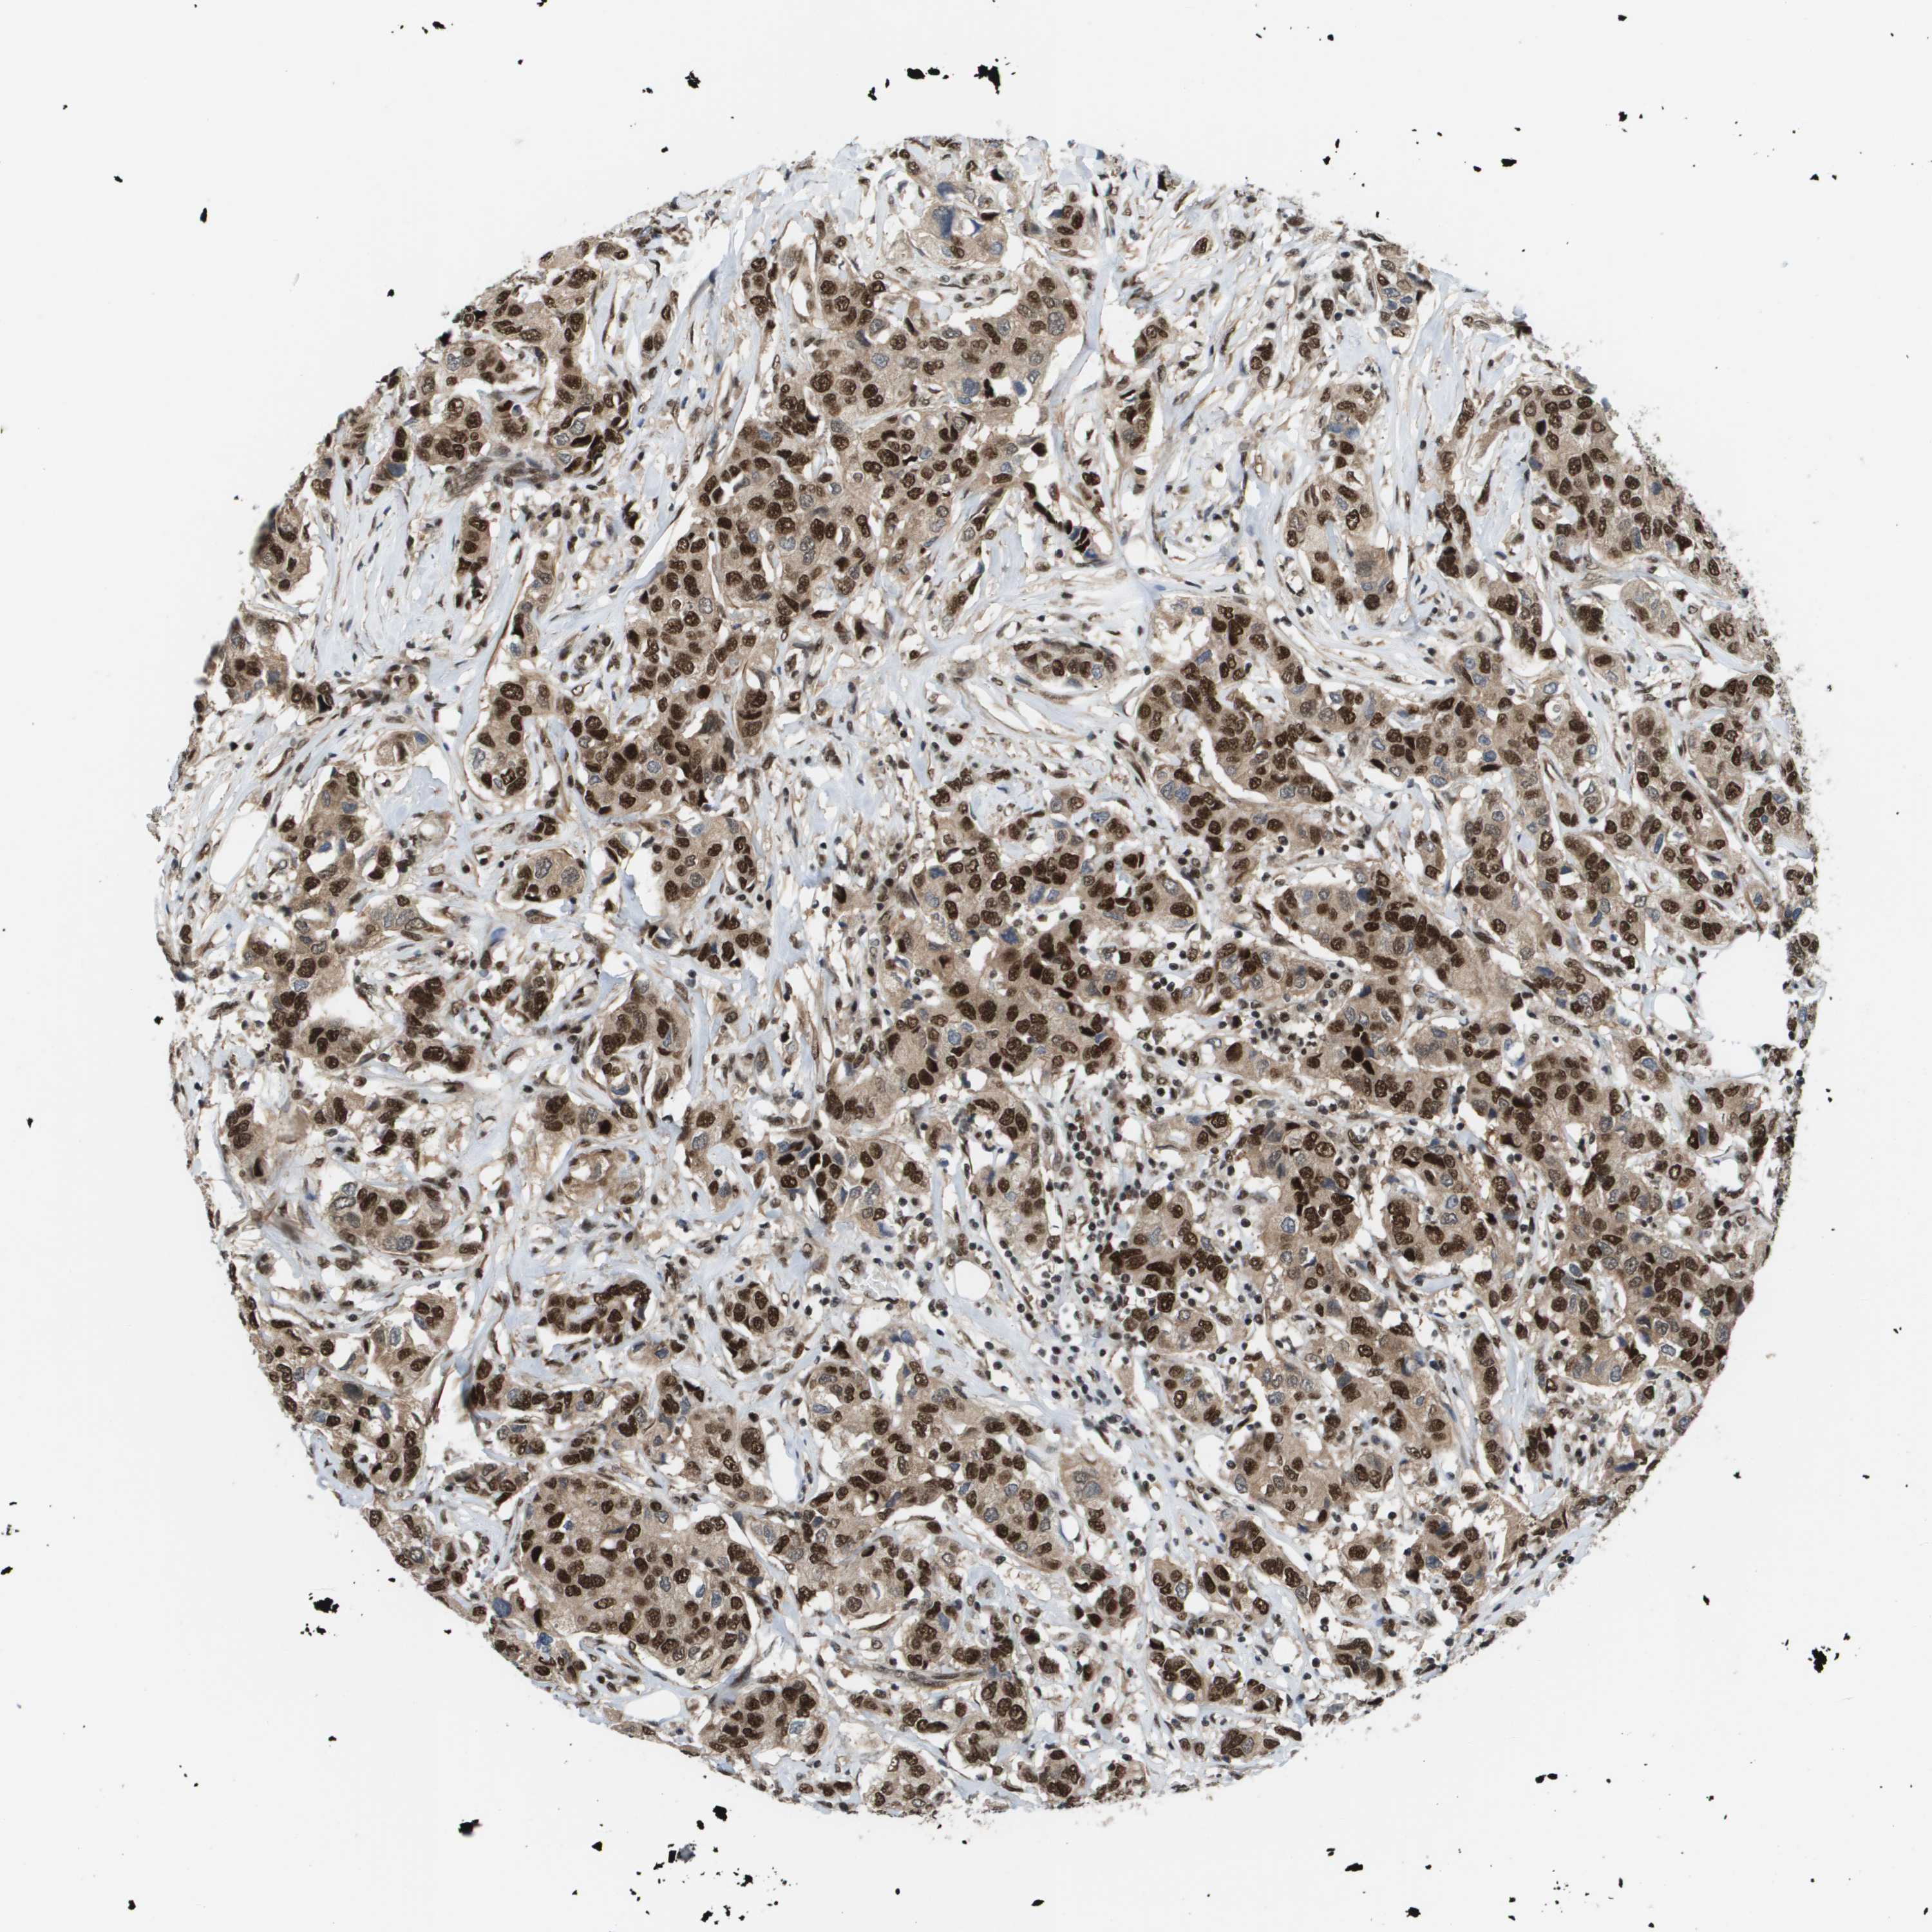

CANCER BREAST CANCER Show tissue menu

BRCA TCGA BRCA VALIDATION PROTEIN EXPRESSION